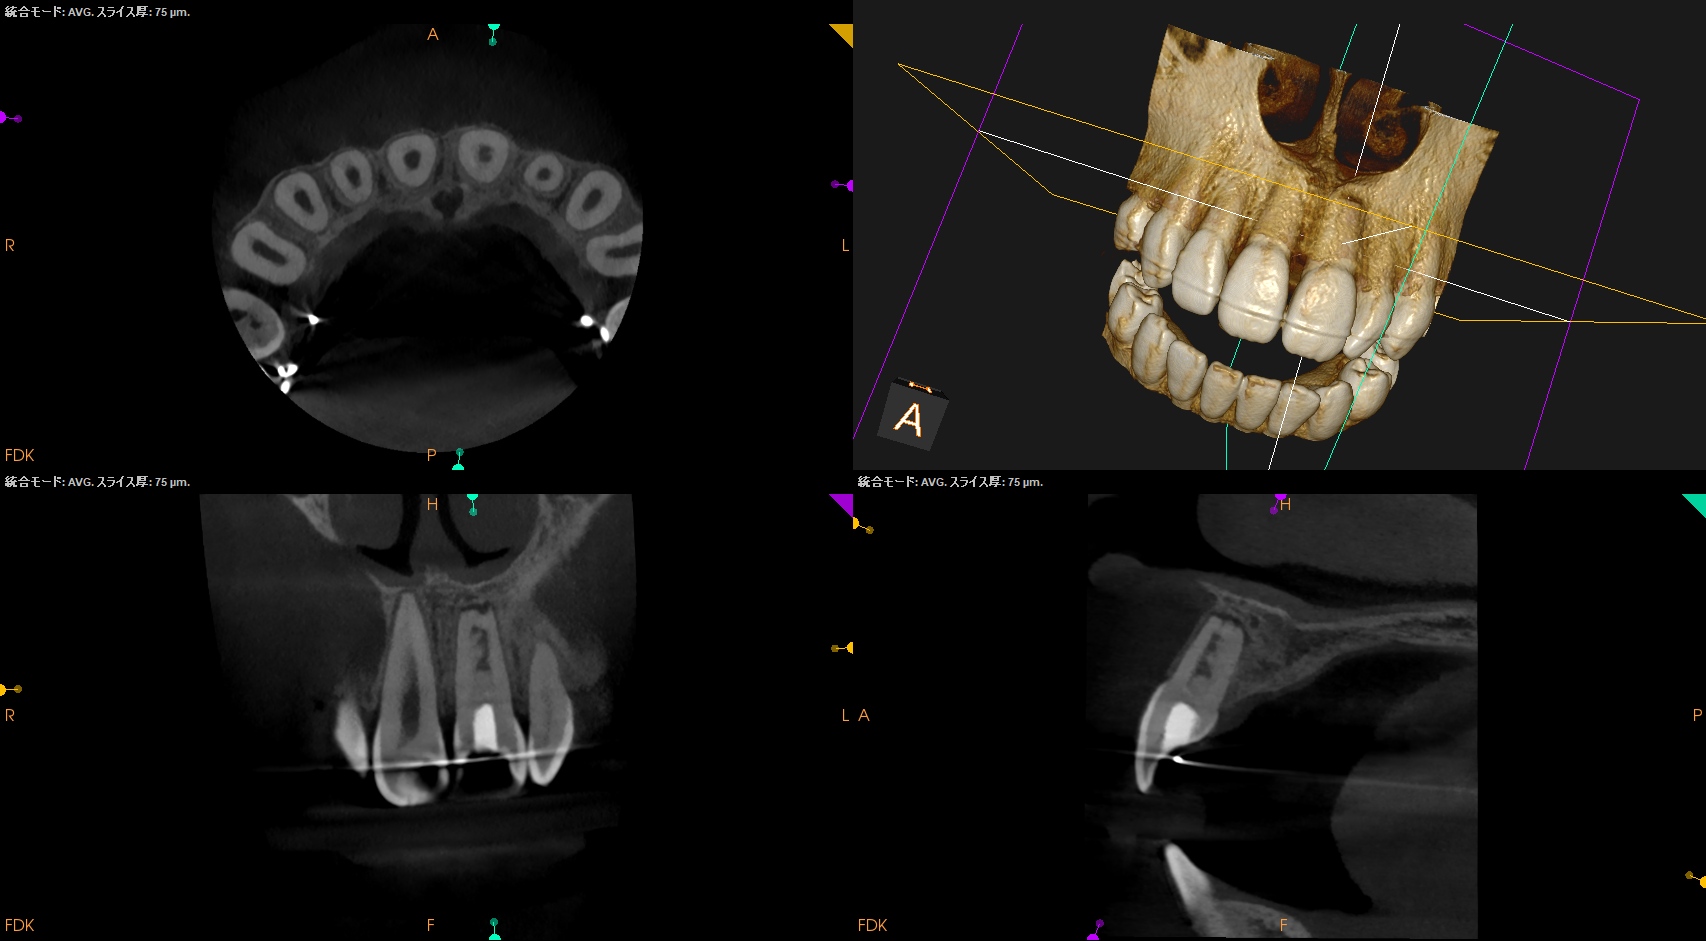

#9 Regeneration 2yr recall(2025.12.12)

初診時、1年経過観察時と比較した。

大きく問題が解決している。